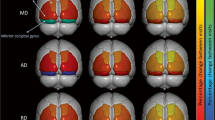

Atlas registration was completed to provide cortical and subcortical (i.e. caudate) brain regions. This was completed using the well-validated Desikan-Killiany brain atlas, an automated labelling system (Desikan et al., 2006). Note, that this atlas automatically generates maps for each hemisphere separately. As such, all analyses were performed calculating mean values for both hemispheres of each brain region in order to minimise the number of multiple comparisons.

Tractography

Whole-brain tractography streamline reconstruction included brain mask generation, response function generation and streamline generation using “Second-order Integration Over Fiber Orientation Distributions” (iFOD2). “Spherical-deconvolution Informed Filtering of Tractograms” (SIFT) was used to improve the quality of tract reconstruction outlined in https://mrtrix.readthedocs.io/en/latest/quantitative_structural_connectivity/sift.html. White matter tractography measures were generated for the tracts of interest using subcortical and cortical parcellations from the Desikan-Killiany brain atlas as noted in the section above.

Using a general linear model (repeated measures ANCOVA), we sought to determine whether white matter integrity changes (FA, AD, RD) occurred in specific tracts from the caudate to regions of interest (Precentral Gyrus, Superior Frontal and Rostral Middle Region), over time in pre-HD and symp-HD, compared to controls.

The primary aim of this study was to examine longitudinal white matter tractography changes in the caudate and precentral, superior frontal and rostral middle frontal brain regions in pre-HD and symp-HD, compared to controls. We did not find a significant interaction effect of Group by Time for any measure in the three regions of interest, nor were there any significant effects of Time. However, we demonstrated significant group differences of FA in the precentral frontal region, AD in the rostral middle frontal region, and RD in the precentral and rostral middle frontal regions with the symp-HD group showing significant differences compared to the pre-HD and control groups (the latter two groups did not differ from one another). Tractography changes were not correlated with change in UHDRS-TMS or DBS in any of the regions of interest.

The finding of significant group level tractography changes in symp-HD from the caudate to the precentral region supports previously established findings that motor circuits are particularly vulnerable in HD (Georgiou-Karistianis & Egan, 2011; Poudel et al., 2014). We found that the symp-HD group had significantly decreased FA, compared to pre-HD and controls, indicating that tracts to the precentral region are likely affected during the symptomatic stage of disease. As HD is primarily a motor disorder, and clinical diagnosis is determined by the development of motor symptoms, it would be expected that white matter connections to the motor cortex would be compromised in symp-HD. Indeed, others have reported similar compromise of the structural connectivity of motor circuits (Georgiou-Karistianis & Egan, 2011; Poudel et al., 2014). In this study, we measured an approximate ~ 4.5% reduction in FA from the caudate to the motor cortex in symp-HD, compared to the FA at baseline, to ~ 2.5% reduction at 30-months. It is unclear why the difference in FA between controls and symp-HD reduced over this time period, but this could be indicative of either selective neurodegeneration or adaptive neuroplasticity (De Erausquin & Alba-Ferrara, 2013; Mole et al., 2016).

Elevated AD was observed in the tracts radiating from the caudate to the rostral middle frontal region in conjunction with significantly increased RD to the precentral and rostral middle regions in symp-HD. These findings were somewhat expected as previous studies had found increased AD and RD in the corpus callosum (Phillips et al., 2013; Rosas et al., 2010) and whole brain (Weaver et al., 2009) in symp-HD, compared to controls (Liu et al., 2016). Whilst an increase in AD can indicate an increased coherence of tracts, this may also be suggestive of a selective neurodegenerative process occurring in symp-HD, which results in fewer neural branches. Alternatively, higher RD may indicate diffusion of water molecules perpendicular to the direction of the tract, potentially reflecting impaired myelin. The rostral middle frontal region houses the dorsolateral prefrontal cortex, which is integral for executive functions including working memory, which is well documented as being impaired in symp-HD compared to controls (Georgiou-Karistianis et al., 2014; Poudel et al. 2015a). Although we did not investigate the relationship between working memory performance and tractography measures in this paper, future studies could utilise this as a measure of functional decline. Together, these findings characterise the potential damage to white matter tracts caused by HD; namely selective neurodegeneration in the rostral middle frontal region accompanied by demyelination of white matter tracts in the precentral and rostral middle frontal regions.

Our 30-month longitudinal study remains the only longitudinal analysis of white matter microstructure changes in both pre- and symp-HD. Although we were unable to identify any interaction effects of Group by Time, which was the primary aim of the study, we did find white matter tractography differences in symp-HD in both the precentral and rostral middle frontal regions, brain regions responsible for motor control and working memory, respectively. Specifically, the symp-HD group had decreased FA in the precentral region, increased AD in the precentral region, and increased RD in the precentral and rostral middle regions compared with the pre-HD and control groups. Although these findings are suggestive of demyelination and selective neurodegeneration that occurs in specific frontal-striatal tracts during the symptomatic stages of disease, longitudinal changes were not detected in the 30-month period observed in this study..